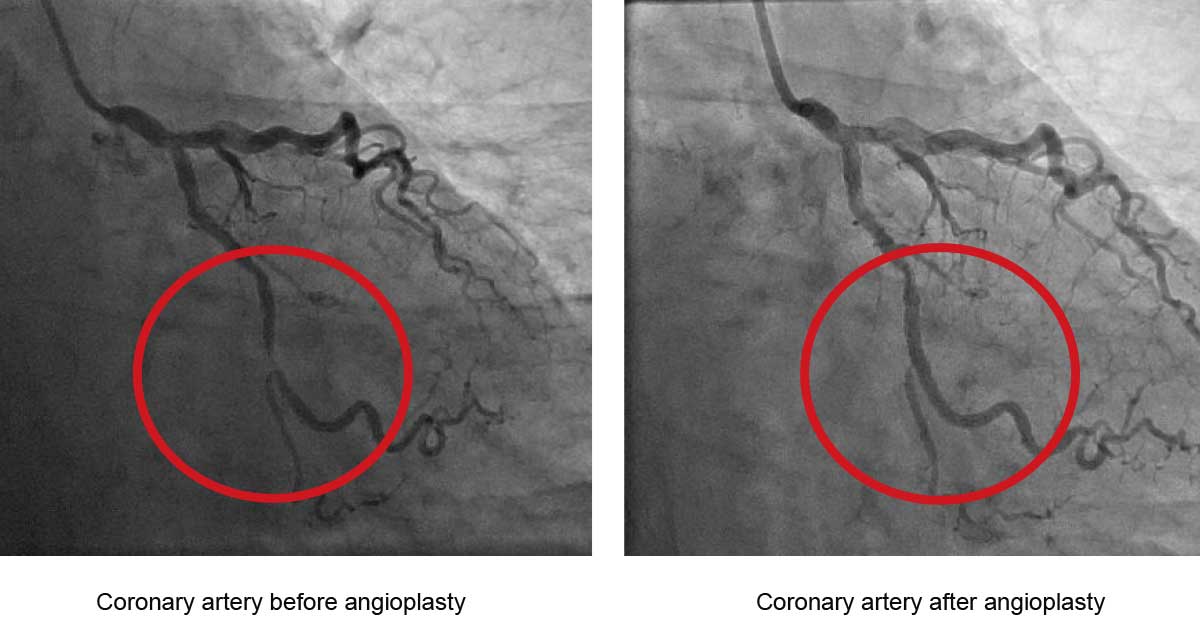

Coronary angioplasty uses a special balloon and a metal mesh tube (stent) to open up a narrowed or blocked coronary artery. In the long term, this should improve blood flow to the heart muscle and result in less or no angina. Angioplasty is sometimes used as an emergency treatment for people that have had a heart attack. You’ll usually have angiography before your angioplasty, but sometimes this is done at the same time.

A stent is a metal mesh tube that can be inserted into a narrowed artery. It acts as an internal support framework to keep the artery open, by continuing to press plaque back against the artery wall. This allows blood to flow freely through the artery.